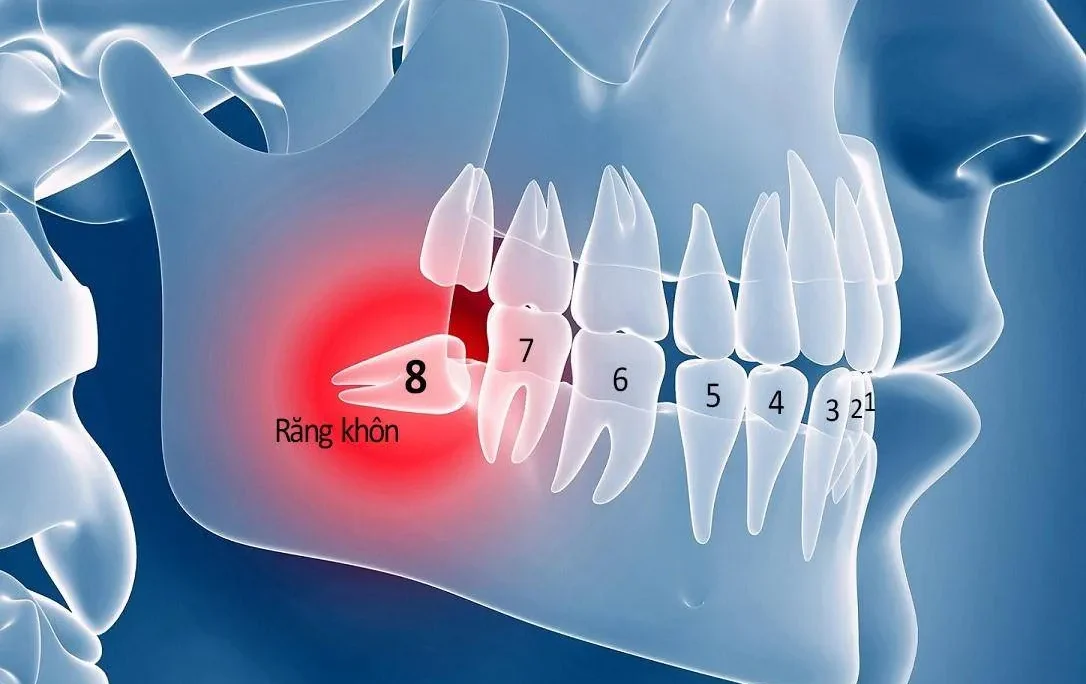

Cấy ghép Implant là một trong những phương pháp phục hình răng mất hiệu quả. Không chỉ cải thiện chức năng ăn nhai, chiếc răng implant còn mang lại giá trị thẩm mỹ. Điều này do răng implant có kết cấu và hình dạng hoàn toàn giống với răng thật. Tuy nhiên để duy trì vẻ đẹp răng implant thì việc chăm sóc răng là vô cùng quan trọng. Trong bài viết này, Nha khoa DrGreen xin chia sẻ tới các bạn các cách chăm sóc răng sau cấy implant như thế nào sao cho hiệu quả

Bác sĩ tiến hành thăm khám, kiểm tra và chụp X-quang. Từ đó xác định tình trạng sức khỏe răng miệng của từng người. Việc kiểm tra có vai trò quan trọng, giúp bác sĩ tư vấn phương pháp điều trị phù hợp. Đồng thời xây dựng kế hoạch phục hình đạt hiệu quả nhất.

Bác sĩ sẽ tiến hành gắn trụ Implant vào xương hàm. Tạo thành chiếc chân răng “nhân tạo” chắc chắn cho mọi người. Nếu cấy nhiều trụ implant hoặc thực hiện phẫu thuật ghép xương, nâng xoang, nong xương… thì cần 2-3 ngày nghỉ dưỡng. Nếu cấy ghép Implant đơn lẻ thì bạn có thể sinh hoạt bình thường hay sau khi gắn trụ.